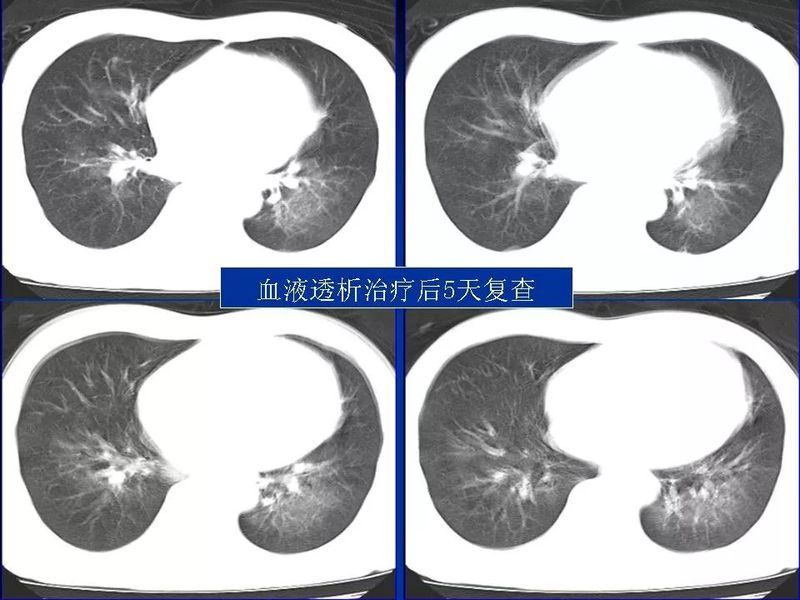

主任提醒:这个病很容易误诊为肺炎!